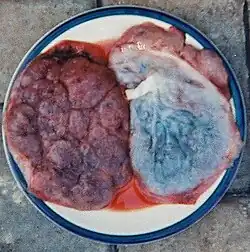

Alumbramiento

Comienza en la expulsión de la placenta, el cordón umbilical y las membranas;[13] esto lleva entre 5 a 30 minutos.[10] El descenso del cordón umbilical por la vulva después del parto es una indicación del desprendimiento final de la placenta, cuanto más sale el cordón, más avanza la placenta hacia fuera de la cavidad uterina. Ese movimiento natural del cordón umbilical proporcional al descenso de la placenta se conoce con el nombre de signo de Ahlfeld.[14]

El desprendimiento de la placenta ocurre en dos posibles mecanismos. El primer desprendimiento ocurre en el centro de la unión útero-placentaria, mecanismo conocido como mecanismo de Baudelocque-Schultze y por lo general se da cerca del 95 % de los casos. Menos frecuente es cuando la placenta se desgarra inicialmente de los lados de la unión útero-placentaria, conocido como el mecanismo de Baudelocque-Duncan. Las contracciones uterinas continúan durante el descenso de la placenta, las cuales ayudan a comprimir los vasos terminales del miometrio que pierden su utilidad después del parto, proceso que se conoce en obstetricia como las ligaduras vivas de Pinard.[15]

Placenta

En algunos grupos culturales hay costumbres rituales hacia la placenta, reconocida como el órgano que hace de nexo entre la madre y el feto y lo alimenta. Por ejemplo, se entierra y en el lugar se planta un árbol. Menos extendida está la costumbre de ingerirla, un hábito denominado placentofagia.[27] La placenta es usada también con fines cosméticos.[cita requerida]